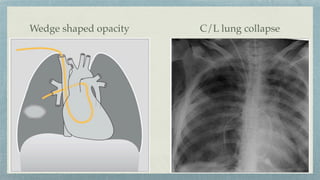

Wedge shaped opacity C/L lung collapse